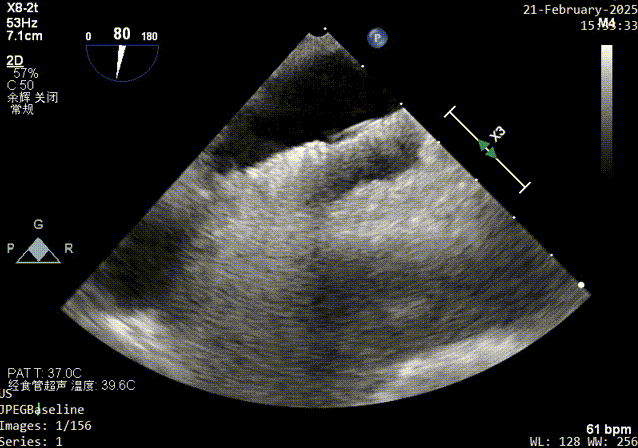

主动脉短轴切面超声影像

经食道超声:房间隔卵阙窝边缘见卵圆瓣闭合不佳,可见一隧道样缝隙,长约16mm,左房面约1.6mm,右房出口约1.0-2.3mm,X-plane短轴切面而测得宽度约10mm,CDFI可在该处探及左向右过血流。原发隔卵圆瓣厚约1.3mm,继发隔厚度约4.4mm,右房面出口距主动脉根部约7mm,距上腔静脉入口约19mm。

1、PFO结构:巨大型PFO,静息状态下房水平左向右分流。继发隔厚约5.7mm;原发隔厚约1.2mm;未见明确下腔静脉瓣及希阿里网回声。

2、PFO参数:隧道裂隙宽约4.4mm ;卵圆孔隧道长度14mm;